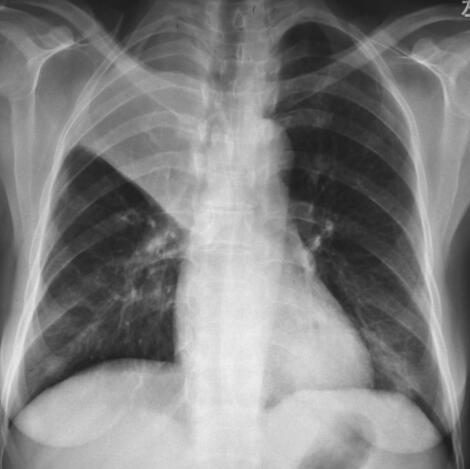

患者,女,52岁,新疆巴楚县农民,维吾尔族。因“间断发热6个月,发现肺部阴影和眼部肿物2个月”于2012年4月10日收入院。患者于6个月前出现间断发热,体温39~40.5℃,伴畏寒、寒战,持续30分钟至3小时可自行降至正常,发热时间间隔2~10天,曾于当地医院行胸片检查“未见明显异常”,给予“头孢类”抗生素治疗无效。2个月前出现双眼不适、右眼视力下降,眼科检查示“右眼肿物”,切除肿物病理示“少许坏死组织”。术前胸片检查发现“右肺上野圆形密度增高影”(图1);肺CT示“右肺上叶团块影,周围见分叶征,内见空洞;左肺下叶球形占位影,周围散在片状渗出影”(图2),遂于当地医院住院诊治。行支气管镜检查发现“右上叶肿物生长,各分支管腔狭窄,右中、下叶各支通畅;左支气管各支通畅”。行左下叶支气管刷检,病理报告“大片炎性渗出及坏死组织”。进而就左肺下叶病变行经皮肺穿刺活检术,病理报告“部分肺泡上皮增生,变性坏死组织炎性细胞浸润”。发热及肺部肿物诊断未明。患者因眼部肿物切除后出现右眼发红、疼痛、视力下降,10天前于我院眼科就诊,诊断为“右眼角膜穿孔、右眼眶蜂窝织炎”,行右眼摘除术,眼球病理示“中性粒细胞浸润,部分组织坏死伴脓性渗出物”。术后5天出现消化道大出血,肠镜示“结肠多发溃疡”,肠黏膜病理示“慢性炎症”,给予输血、止血治疗后出血停止。因发热和肺部肿物原因不明,为进一步诊治收入我科。近1个月患者发热呈持续性,体温39~40℃。10天前眼科术前复查胸片显示“右上叶不张”(图3);肺CT发现“右肺上叶阻塞性肺不张,左肺团块影,周围见片状渗出影”(图4)。患者发病以来,食欲不振、乏力明显,近半年体重下降5kg。

图4 肺部CT

右肺上叶阻塞性肺不张,左肺团块影,周围见片状渗出影,较前增大